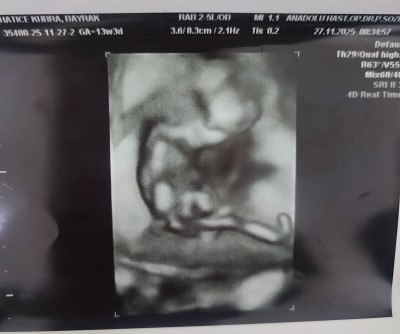

11 haftalık ve 13+5 haftalık ultrason görüntülerimiz doktor cinsiyette emin olamadi önce erkek sonra kız dedi ama sizin tahminleriniz neler?

Gebelik haftası 13+5